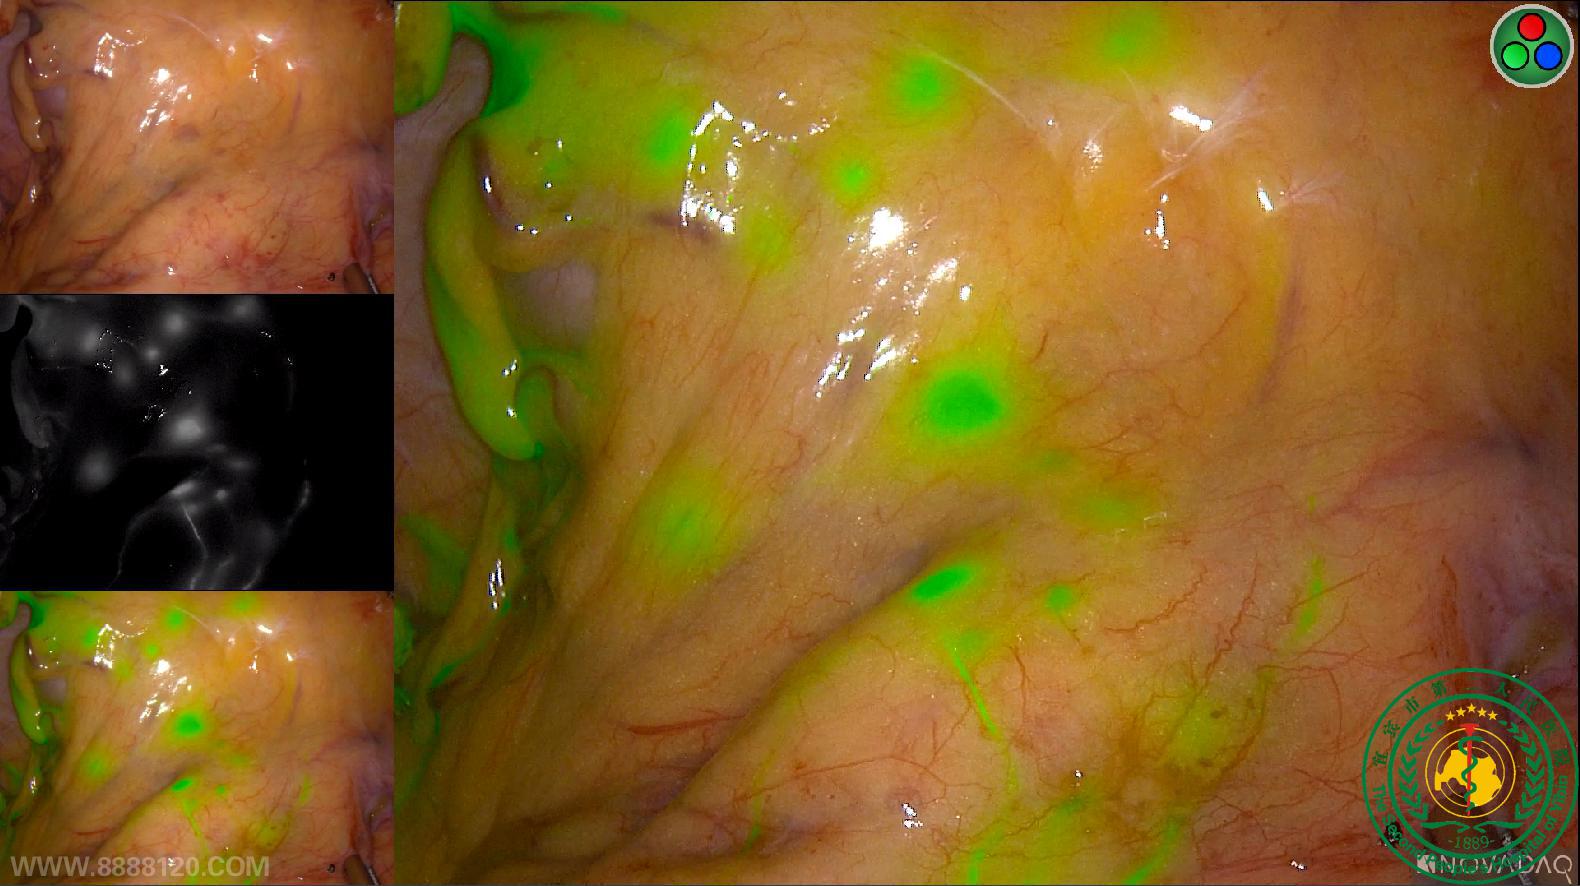

我院胃肠外科成功开展四川省第一例荧光腹腔镜直肠癌NOSES手术

我院胃肠外科成功开展四川省第一例荧光腹腔镜直肠癌NOSES手术16556